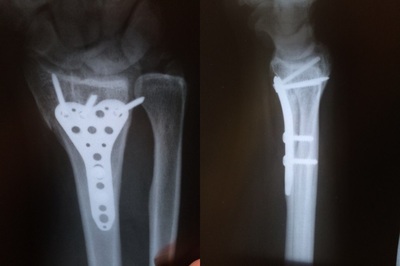

Швы недавно сняли. Рукой немного двигаю, но пока боюсь что-то делать. Пластину из-за гематомы не чувствую, но чувство, что что-то в руке мешает. В больнице сказали год или два с ней ходить. Но это место останется уязвимым.

Год ходить - не страшно, поверьте! А вот после того, как ее снимают, оооочень странные ощущения.. Все таким ненадежным кажется (я про кости и мыщцы)..

Локтевой сустав - это вообще караул(( главное, чтобы восстановилась подвижность! Выздоравливайте!